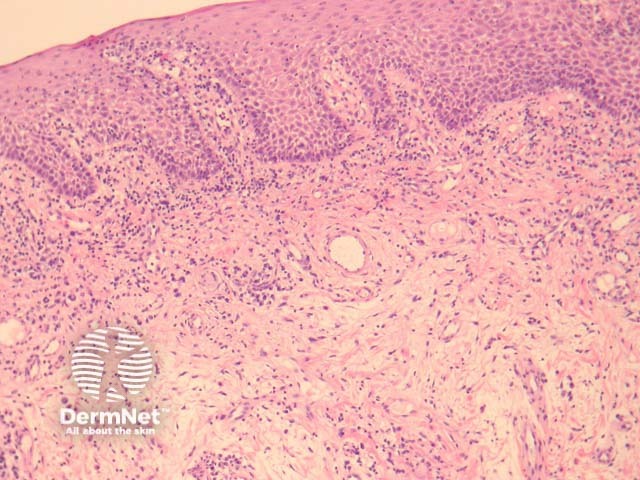

In orofacial granulomatosis, sections show oral mucosa with a sparse inflammatory infiltrate and mild oedema (figure 1). Higher power examination shows ectasia of lymphatics next to rare loose granulomas (figures 2-4, arrows indicate granulomas). Sometimes the granulomas may be difficult to find and extensive serial sectioning of the biopsy is recommended.

Figure 1